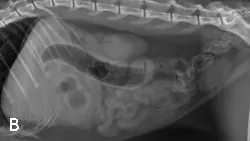

A brief abdominal ultrasound was performed and the foreign body was confirmed in a small intestinal lumen.

Outcome: This patient was cut! He was treated for dehydration and taken to surgery, where a rectangular plastic foreign body was “milked” from its location in the jejunum, backwards into the stomach, where a single gastrotomy was performed to remove the object. The severe gastroduodenal distension was secondary to complete obstruction. The patient recovered quickly and ate that same evening.